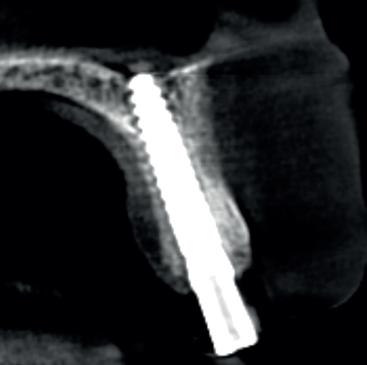

Verticaal botverlies & korte implantaten - De resorptie treedt soms overwegend verticaal op, waardoor de processus alveolaris geheel verdwijnt en er slechts een minimale hoeveelheid basaal/ residuaal bot overblijft. In de mandibula kan dit leiden tot een zeer lage kaak, met mediane kaakhoogtes tot nog maar 4-5 mm (potlood dikte!). Voorheen werd hier een transmandibulair implantaat geplaatst, omdat werd geanticipeerd op breuk [Powers et al, 1994], of werd gekozen voor het verticaal opbouwen van de mandibula: de klassieke absolute kaakverhoging. Tegenwoordig wordt het plaatsen van twee of vier korte implantaten met een lengte van slechts 4-8 mm beschouwd als een goed alternatief voor een augmentatie van de onderkaak (afbeelding 2). Dit scheelt aanmerkelijk in de belasting van de patiënt (minder ingrepen, geen narcose, kortere behandelduur, minimale morbiditeit) en levert goede resultaten op [Vazouras K et al, 2020; Telleman G, et al. 2013; Renouard F and Nisand D. 2006; Guljé F et al. 2012]

Horizontaal botverlies en mini-implantaten - Een geheel andere anatomische situatie ontstaat bij een meer horizontaal resorptiepatroon. Hierbij blijft de kaakhoogte vrijwel volledig intact, maar neemt de dikte van de processus alveolaris af tot een minimum van slechts enkele millimeters. Indien sprake is van een dergelijke zeer dunne processus alveolaris in de maxilla of mandibula, kan ervoor worden gekozen om gebruik te maken van mini-implantaten (implantaten met een diameter < 2.5 tot 3 mm, afbeeldingen 3a-b), als alternatief op een chirurgische kaakverbreding door middel van ‘buccal plating’ met een autoloog bottransplantaat. Het gebruik van mini-implantaten bespaart de patiënt pre-implantologische chirurgie, lange behandelduur, morbiditeit en de noodzaak tot herhaalde aanpassingen van de prothese. Door mini-implantaten flapless te plaatsen wordt de morbiditeit tot een minimum gereduceerd. Hiervoor is echter wel 3D-planning vooraf een vereiste alsook statische navigatie bij het plaatsen door middel van een dwingende boormal, vanwege de zeer geringe marges (zie casus, afbeeldingen 4a-q ). Een bijkomend voordeel van mini-implantaten is, dat ze uit één geheel bestaan en standaard zijn voorzien van

2. Kaakhoogte van 7 mm, twee tissuelevel implantaten van 7 mm lengte geplaatst (Nobel Biocare, Replace Select TC)